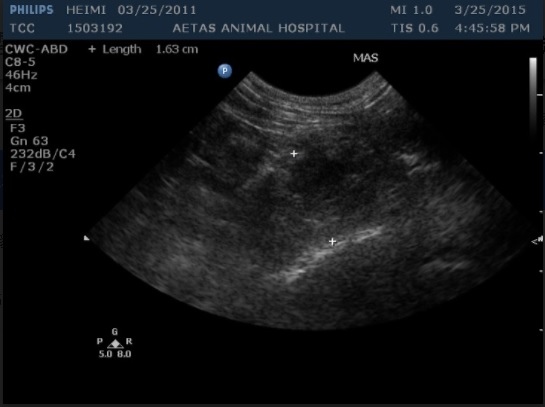

當天的檢驗腹腔超音波發現脾臟前方有腫塊,理學檢查肩頰前淋巴結腫大,腫塊細針採樣後確診為淋巴癌。

圖一: 脾臟前方出現1.63cm 腫塊。